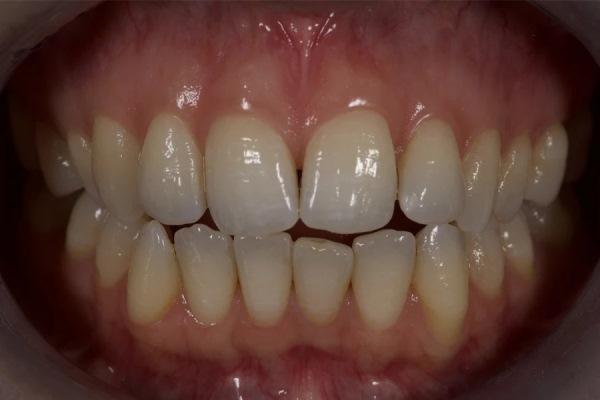

Фото 12. Окончательный результат после ортодонтического лечения. Отмечаются закрытие открытого прикуса, коррекция торка/выравнивание осей зубов и формирование окклюзионных контактов по сравнению с исходным состоянием.